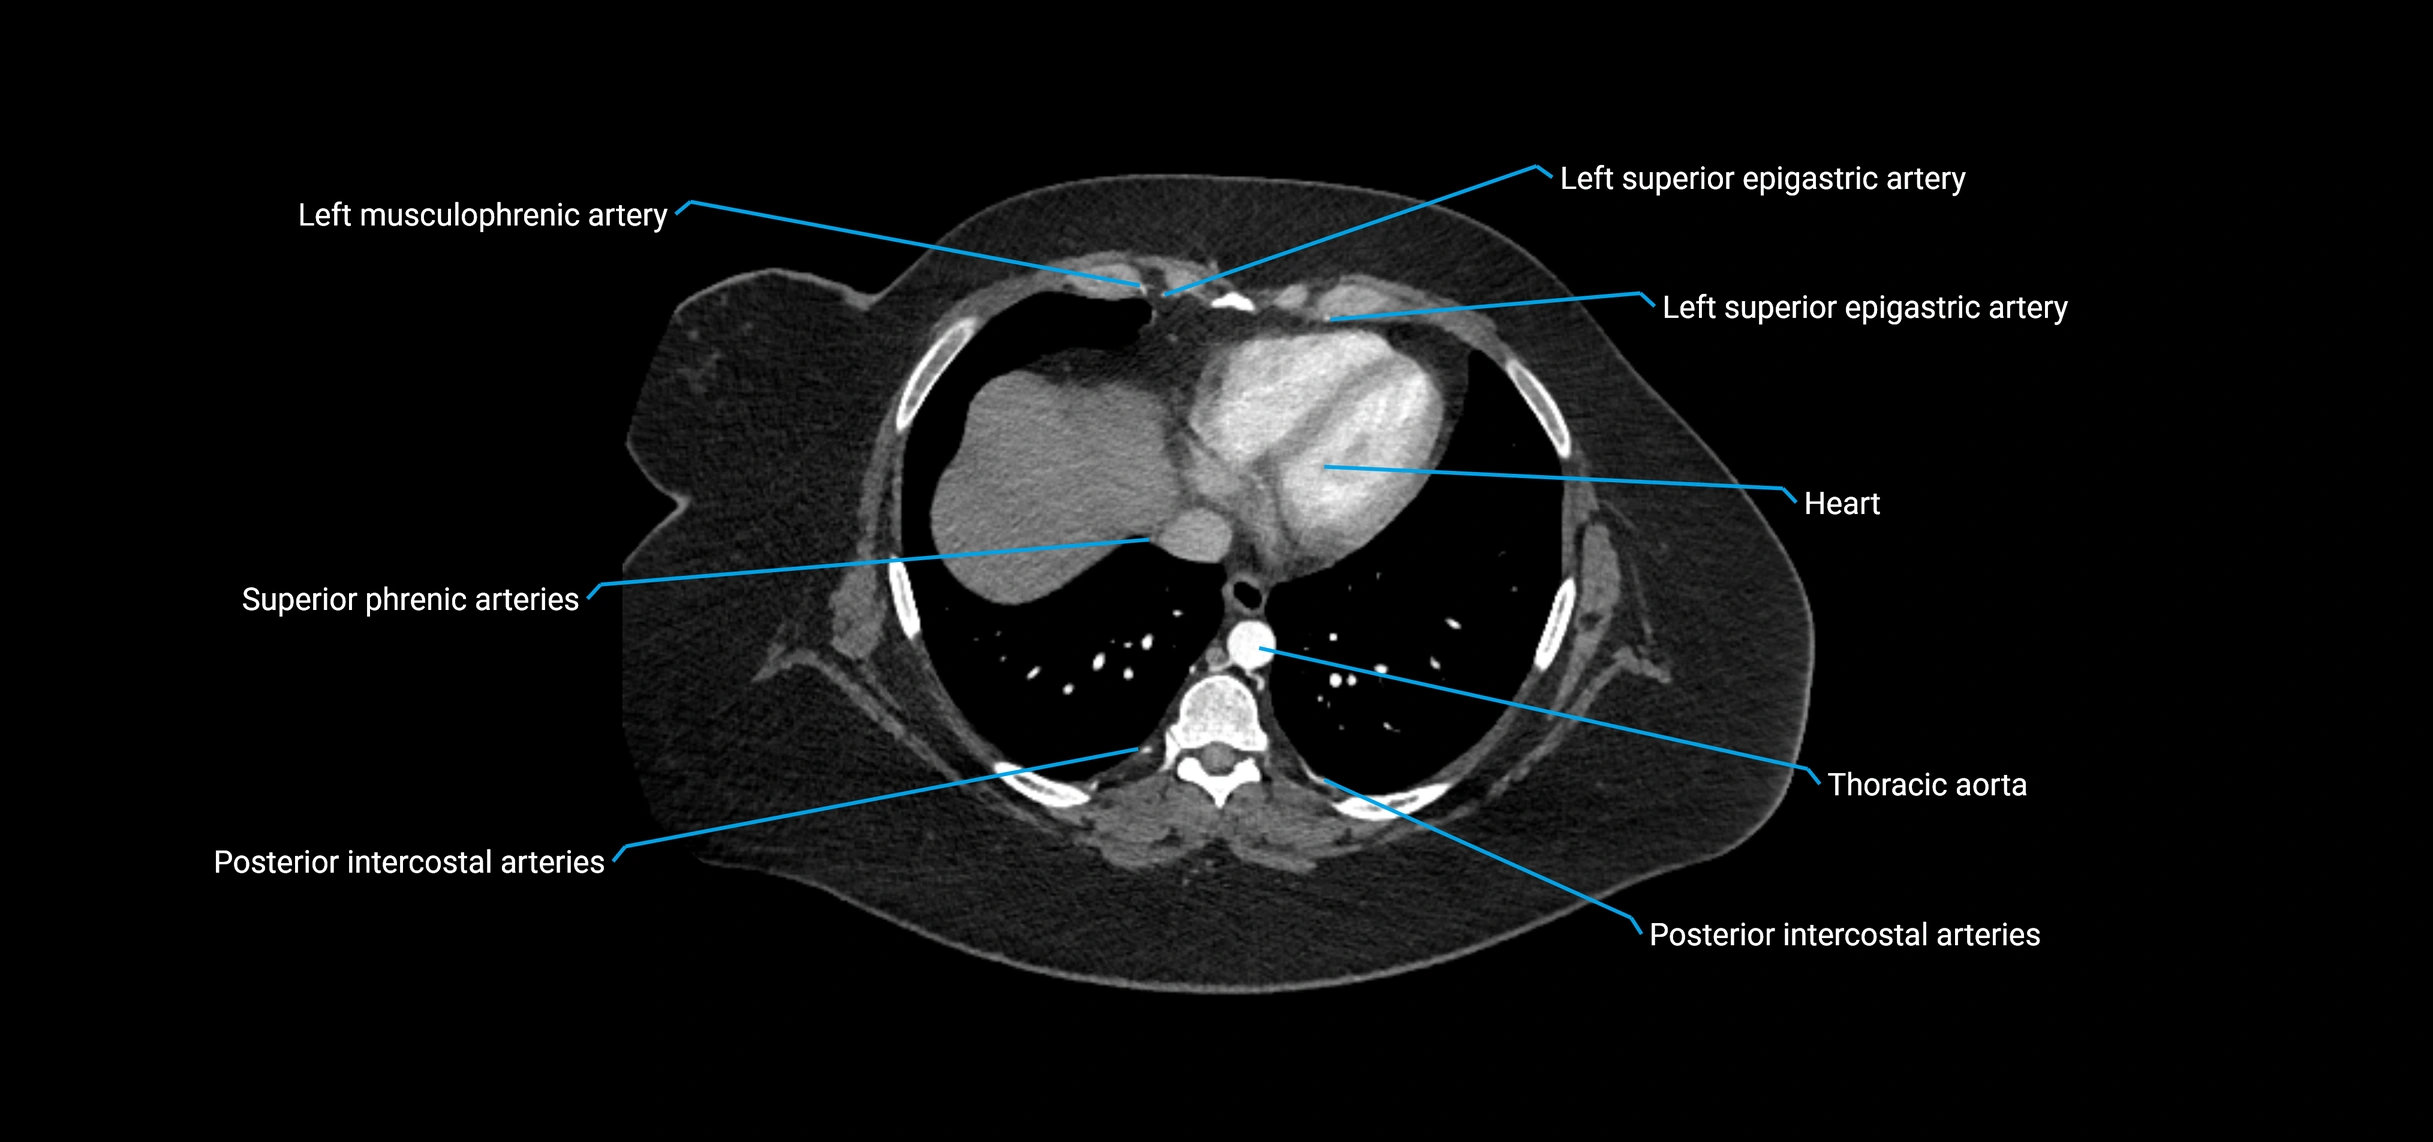

Contrast-enhanced CT (CTA):

• Gold standard for abdominal aortic imaging

• Provides excellent detail of lumen, wall, aneurysm, thrombus, and branch vessels

• Multiplanar and 3D reconstructions help in aneurysm measurement, stent graft planning, and dissection evaluation

• Detects acute rupture, traumatic injury, or occlusion with high sensitivity